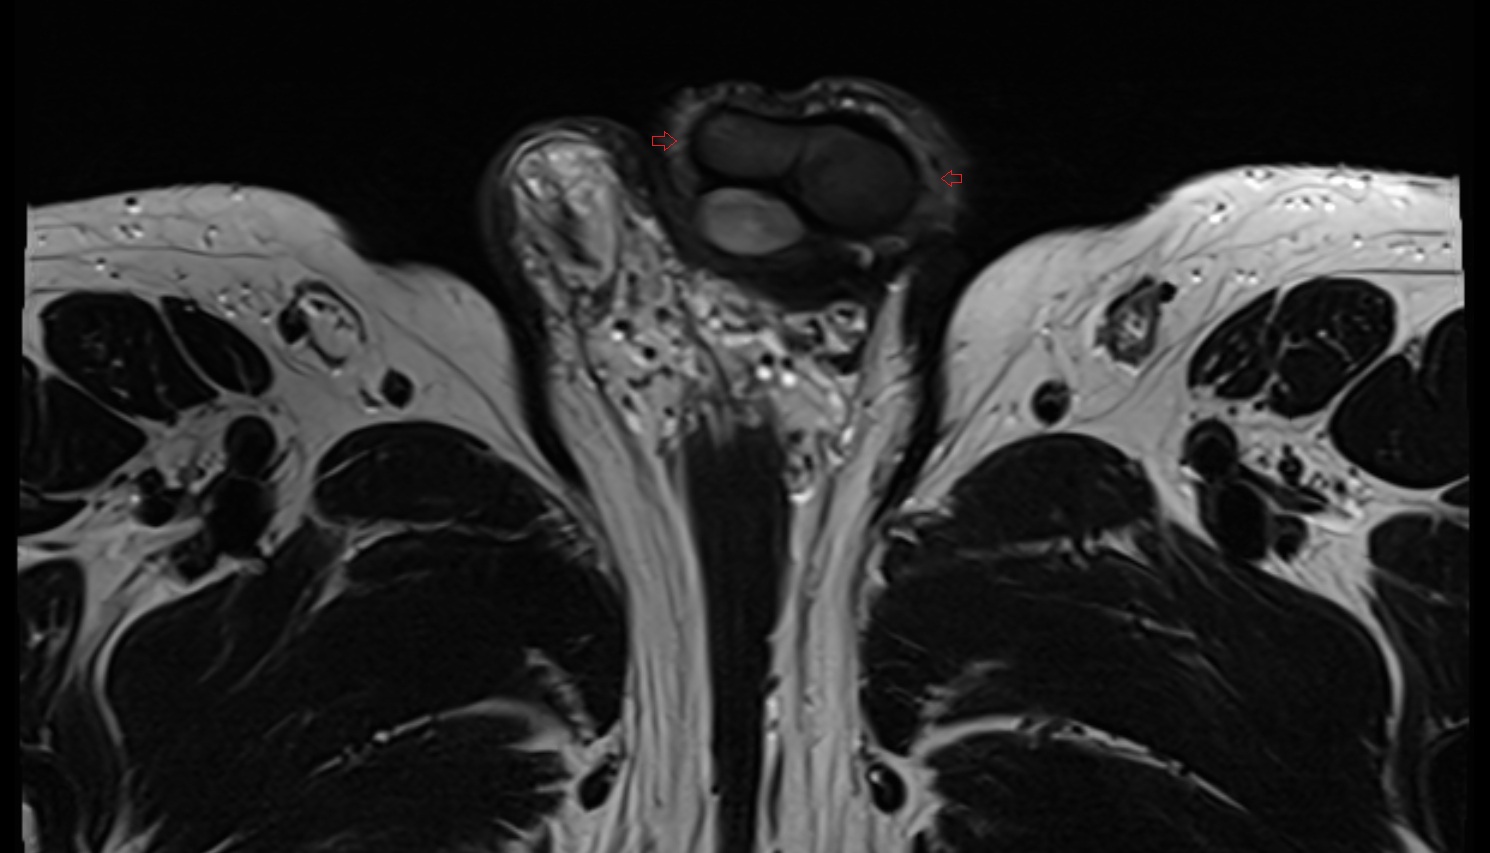

- Peripheral zone of prostate

- Anterior Fibromuscular Stroma of prostate

- Central zone of prostate

- Transitional zone of prostate